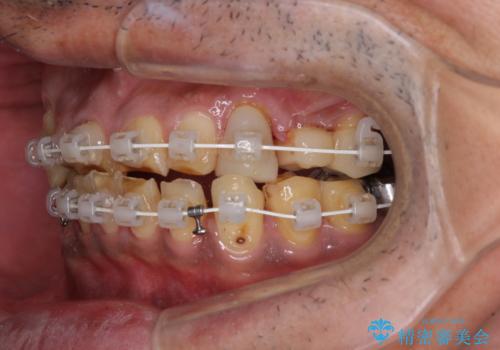

- 矯正装置

- 審美装置

奥歯の欠損が散見されており、銀歯の装着されている歯も多いため、ワイヤー矯正にて歯列を調整し、その後オールセラミッククラウンにて補綴治療を行うこととしました。

矯正治療は想定通り長期化しましたが、しっかりと奥歯の咬み合わせを向上させて前歯の被蓋を改善させることができました。

目立つ銀歯やすり減った前歯がセラミッククラウンとなり、患者様には大変満足していただけました。